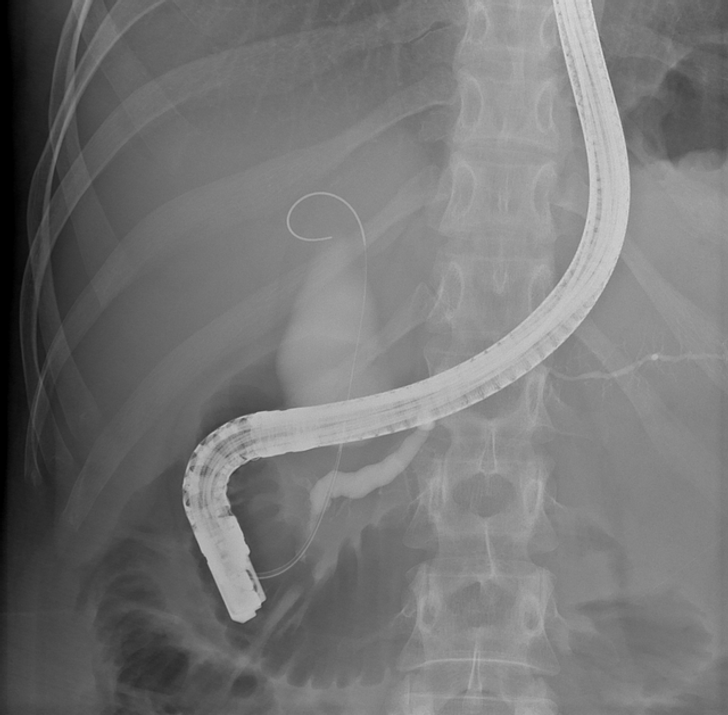

Рентген, зроблений під час ендоскопії